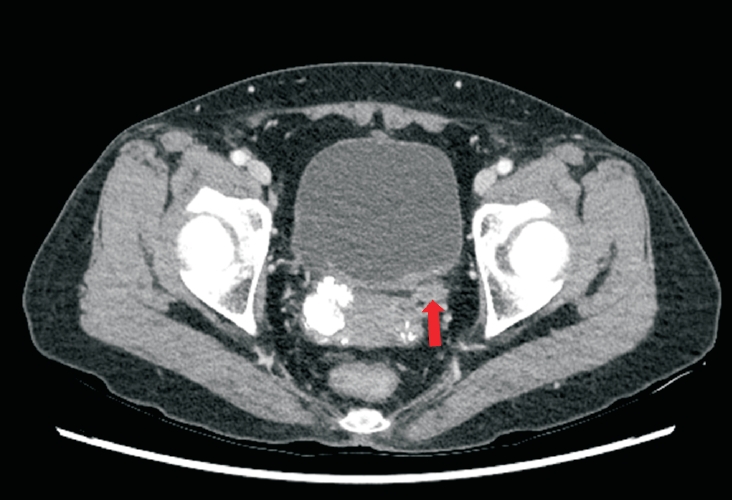

Primary localized amyloidosis confined to the urinary tract is uncommon and frequently misinterpreted due to clinical and radiologic overlap with more prevalent conditions. We describe a 69-year-old woman who experienced recurrent gross hematuria over 2 years and underwent initial transurethral resection based on a presumptive diagnosis of chronic cystitis. Subsequent evaluation revealed a left ureteral mass with hydronephrosis, raising concern for malignancy. Histopathologic examination of both bladder and ureteral specimens demonstrated amorphous eosinophilic deposits that stained positive with Congo red and showed apple-green birefringence under polarized microscopy. Immunofluorescence confirmed λ-light-chain predominance, establishing AL (amyloid light chain)-type amyloidosis without systemic involvement. The patient underwent complete endoscopic resection and remains asymptomatic during ongoing surveillance. This case highlights the diagnostic challenges posed by localized urinary amyloidosis and underscores the importance of histologic confirmation in atypical inflammatory lesions.